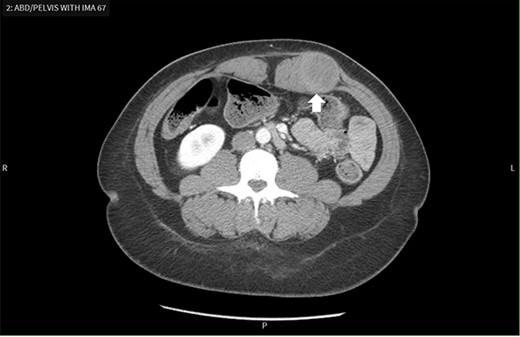

Contrast-enhanced CT scan demonstrates a mass within the left rectus sheath.

Oftentimes, ultrasound is preferred as the first imaging modality [1]. If there is significant concern for malignancy or distant metastasis, a CT should be first [1]. In our patient, contrast enhanced CT was the first imaging modality obtained and revealed a 4.3 × 3.3 × 4.1 cm round mass low in attenuation within the left rectus sheath (Fig. 1). The mass appeared to be an intramuscular lesion with no intraperitoneal extension. A chronic seroma secondary to prior abdominal surgery or a desmoid tumor was discussed as possible differentials.